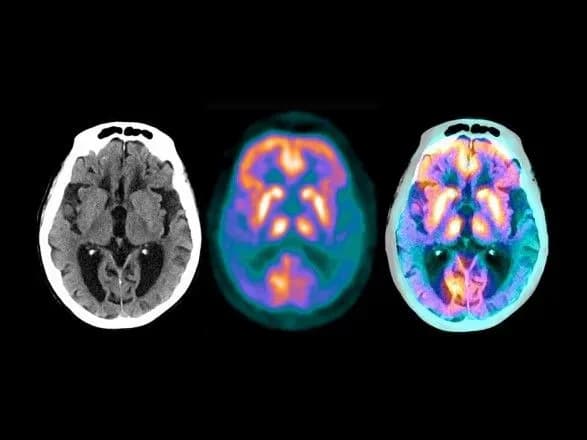

У своєму дослідженні вчені за допомогою штучного інтелекту вивчили дані пацієнтів з хворобою Альцгеймера і COVID-19. Вони виміряли близькість між генами/білками пацієнтів з SARS-CoV-2 і генами, пов'язаними з декількома неврологічними захворюваннями, де більша близькість передбачає наявність пов'язаних або спільних шляхів захворювання. Дослідники також проаналізували генетичні фактори, які дозволили SARS-COV-2 інфікувати тканини і клітини мозку.

"Хоча дослідники виявили мало доказів того, що вірус націлений безпосередньо на мозок, вони виявили тісні мережеві зв'язки між вірусом і генами/білками, пов'язаними з декількома неврологічними захворюваннями, передусім з хворобою Альцгеймера, вказуючи на шляхи, за якими COVID-19 може призвести до деменції, подібної до хвороби Альцгеймера", - йдеться в повідомленні.

Далі вчені досліджували потенційний зв'язок між COVID-19 і нейрозапаленням і пошкодженням мікросудин головного мозку, які є відмінними ознаками хвороби Альцгеймера.

"Ми виявили, що інфекція SARS-CoV-2 значно змінила маркери хвороби Альцгеймера, залучені в запалення мозку", - вказав провідний автор дослідження доктор Фейсюн Чен.

"Ці дані показують, що вірус може впливати на кілька генів або шляхів, що беруть участь в нейрозапаленні і пошкодженні мікросудин головного мозку, що може призвести до когнітивних порушень, подібних до хвороби Альцгеймера", - додав він.